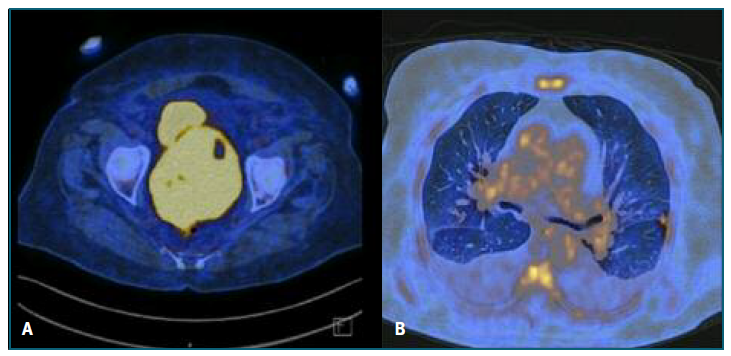

88 years old, obstetric index 3003, menopause at 58 years old, with a history of arterial hypertension, obesity, type 2 diabetes mellitus, dyslipidemia, and asthma. She was admitted to the emergency department with a 2 week vaginal blood loss. Physical examination revealed moderate quantity of blood in the vagina; an enlarged, globular, and hard elastic cervix, with exuberant vessels, one of which was bleeding; abdominal distention was also observed. Transvaginal ultrasound showed an anteverted uterus, increased in volume, with a well-defined vascularized mass in the isthmic region, measuring 6x4 cm. The endometrium was distorted, irregular with a thickness of about 8 mm. An uterine cervix biopsy was performed, revealing a high-grade CD20+ Non-Hodgkin B Lymphoma, with morphology and immunohistochemical profile compatible with diffuse large B cell lymphoma, molecular subtype GCB (Hans algorithm); high ki67 proliferative index (upper 80%). The patient was referred for a hematology oncology appointment. One week after the diagnosis, the patient was hospitalized for a new episode of abundant vaginal blood loss, requiring transfusional support (2 units of red blood cells). In an additional imaging study (PET), there was a large mass centered in the cervix region, with approximately 113x94 mm, multiple focal areas distributed throughout the uterine body and several nodular lesions in both lungs, suggestive of lymphomatous lesions - stage IV-A in the Ann Arbor classification (Figure 3). A combined chemoimmuno-therapy regimen was instituted, with rituximab, cyclo-phosphamide, doxorubicin, vincristine, and prednisolone (R-CHOP). Were completed 6 cycles, with no fur-ther evidence of blood loss and good clinical response after 9 months of follow-up.